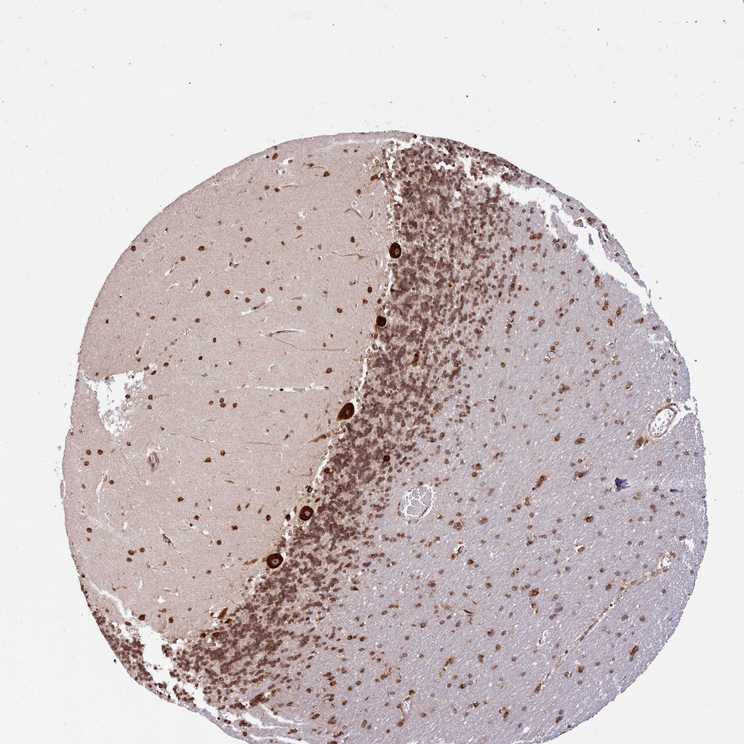

BRAIN CEREBELLUM Show tissue menu

CEREBELLUM - Expression summary

CEREBELLUM - Antibody stainingi

Antibody staining in the annotated cell types in the current human tissue is reported as not detected, low, medium, or high, based on conventional immunohistochemistry profiling in selected tissues. This score is based on the combination of the staining intensity and fraction of stained cells.

Each image is clickable and will lead to virtual microscopy that enables deeper exploration of all samples and also displays staining intensity scores, fraction scores and subcellular localization as well as patient and tissue information for each sample.

Antibody HPA039306Antibody HPA039673

Purkinje cells MediumHigh

Cells in granular layer Not detectedMedium

Cells in molecular layer Not detectedHigh